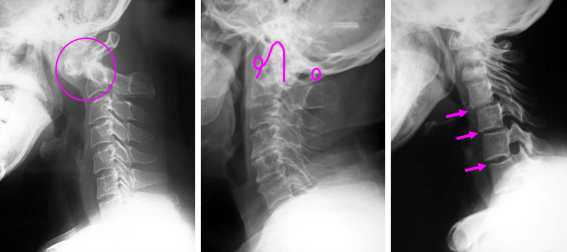

女性に多く、関節リウマチによる四肢関節炎が進行すると、頚椎にも異常をきたします。関節リウマチの診断は、症状、身体診察、血液検査などにより、リウマチ性脊椎炎は画像検査(X線、CT、MRI)に基づいて行われます。病初期は上位頚椎(第1-2頚椎)の関節が破綻し、環軸関節亜脱臼(AAS)を呈します。次第に垂直性亜脱臼(VS)に進行し、末期では第3-7頚椎に軸椎下亜脱臼(SAS)を呈します。病初期のAASでは、頚部痛が主体の症状が多く、第1-2頚椎の不安定性が強い場合や進行性の麻痺症例では手術が必要になります。VSやSASでは、頭蓋底陥入症や脊髄の圧迫による症状が出現し、積極的な手術が必要になる事が多いのが特徴です。 近年では、生物学的製剤などの普及により、リウマチ性脊椎炎の発生頻度は低くなっていますが、未治療あるいは治療に反応しづらい関節リウマチによるリウマチ性脊椎炎では、なお外科的な治療が必要な事があります。石井賢医師は、日本整形外科学会認定リウマチ医であり、これまで多くのリウマチ性脊椎炎の治療を担当しています。

図 (左)環軸関節亜脱臼(AAS)(まん中)垂直性亜脱臼(VS)(右)軸椎下亜脱臼(SAS)